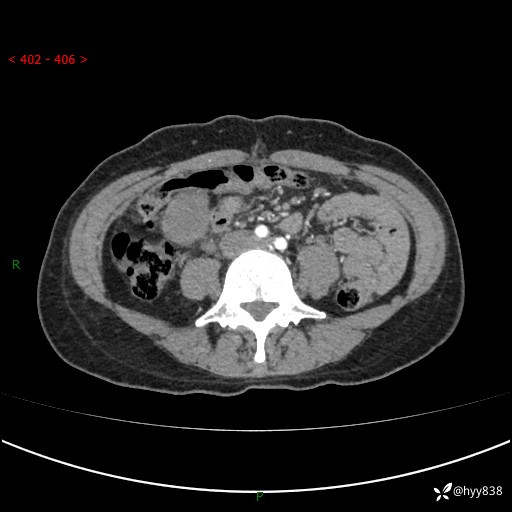

年轻女性,发现腹腔肿物1周。圆圆的肿物,诊断有难度---结果公布~

现病史:患者自诉于1周前无明显诱因出现剑突下间断性隐痛,尚可忍受,不向其它部位放射,无恶心呕吐、腹泻便秘等不适,于当地市第二人民医院就诊,行CT结果示:1.右中腹占位,间叶组织来源可能2.小肠梗阻3.盆腔积液4.腹腔积液5.副脾6.肝囊肿;于荆州二医行抗炎,抑酸,护胃,补液等对症支持治疗;患者病情好转,今为求进一步诊治,遂来我院门诊就诊,门诊以“腹腔肿瘤”收入院。 起病以来,患者精神、睡眠、饮食一般,大小便正常,近期体力体重无明显改变。

腹部CT增强(外院平扫)